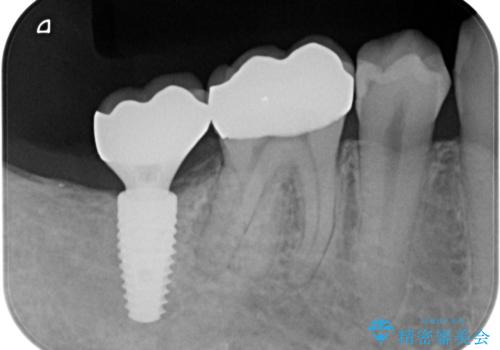

右下の被せ物を外し虫歯を除去したところ虫歯が深く保存が難しい状態だったので抜歯を行いました。

手前の銀の詰め物のところは除去して拡大鏡下で虫歯を取り除き、ジルコニアクラウンで治療を行いました。

抜歯したところは抜歯後骨の治癒を待ち、CTを撮影しインプラント治療ができる事(骨の厚みなど)確認し治療を行いました。

白くて綺麗な被せ物が入りました。